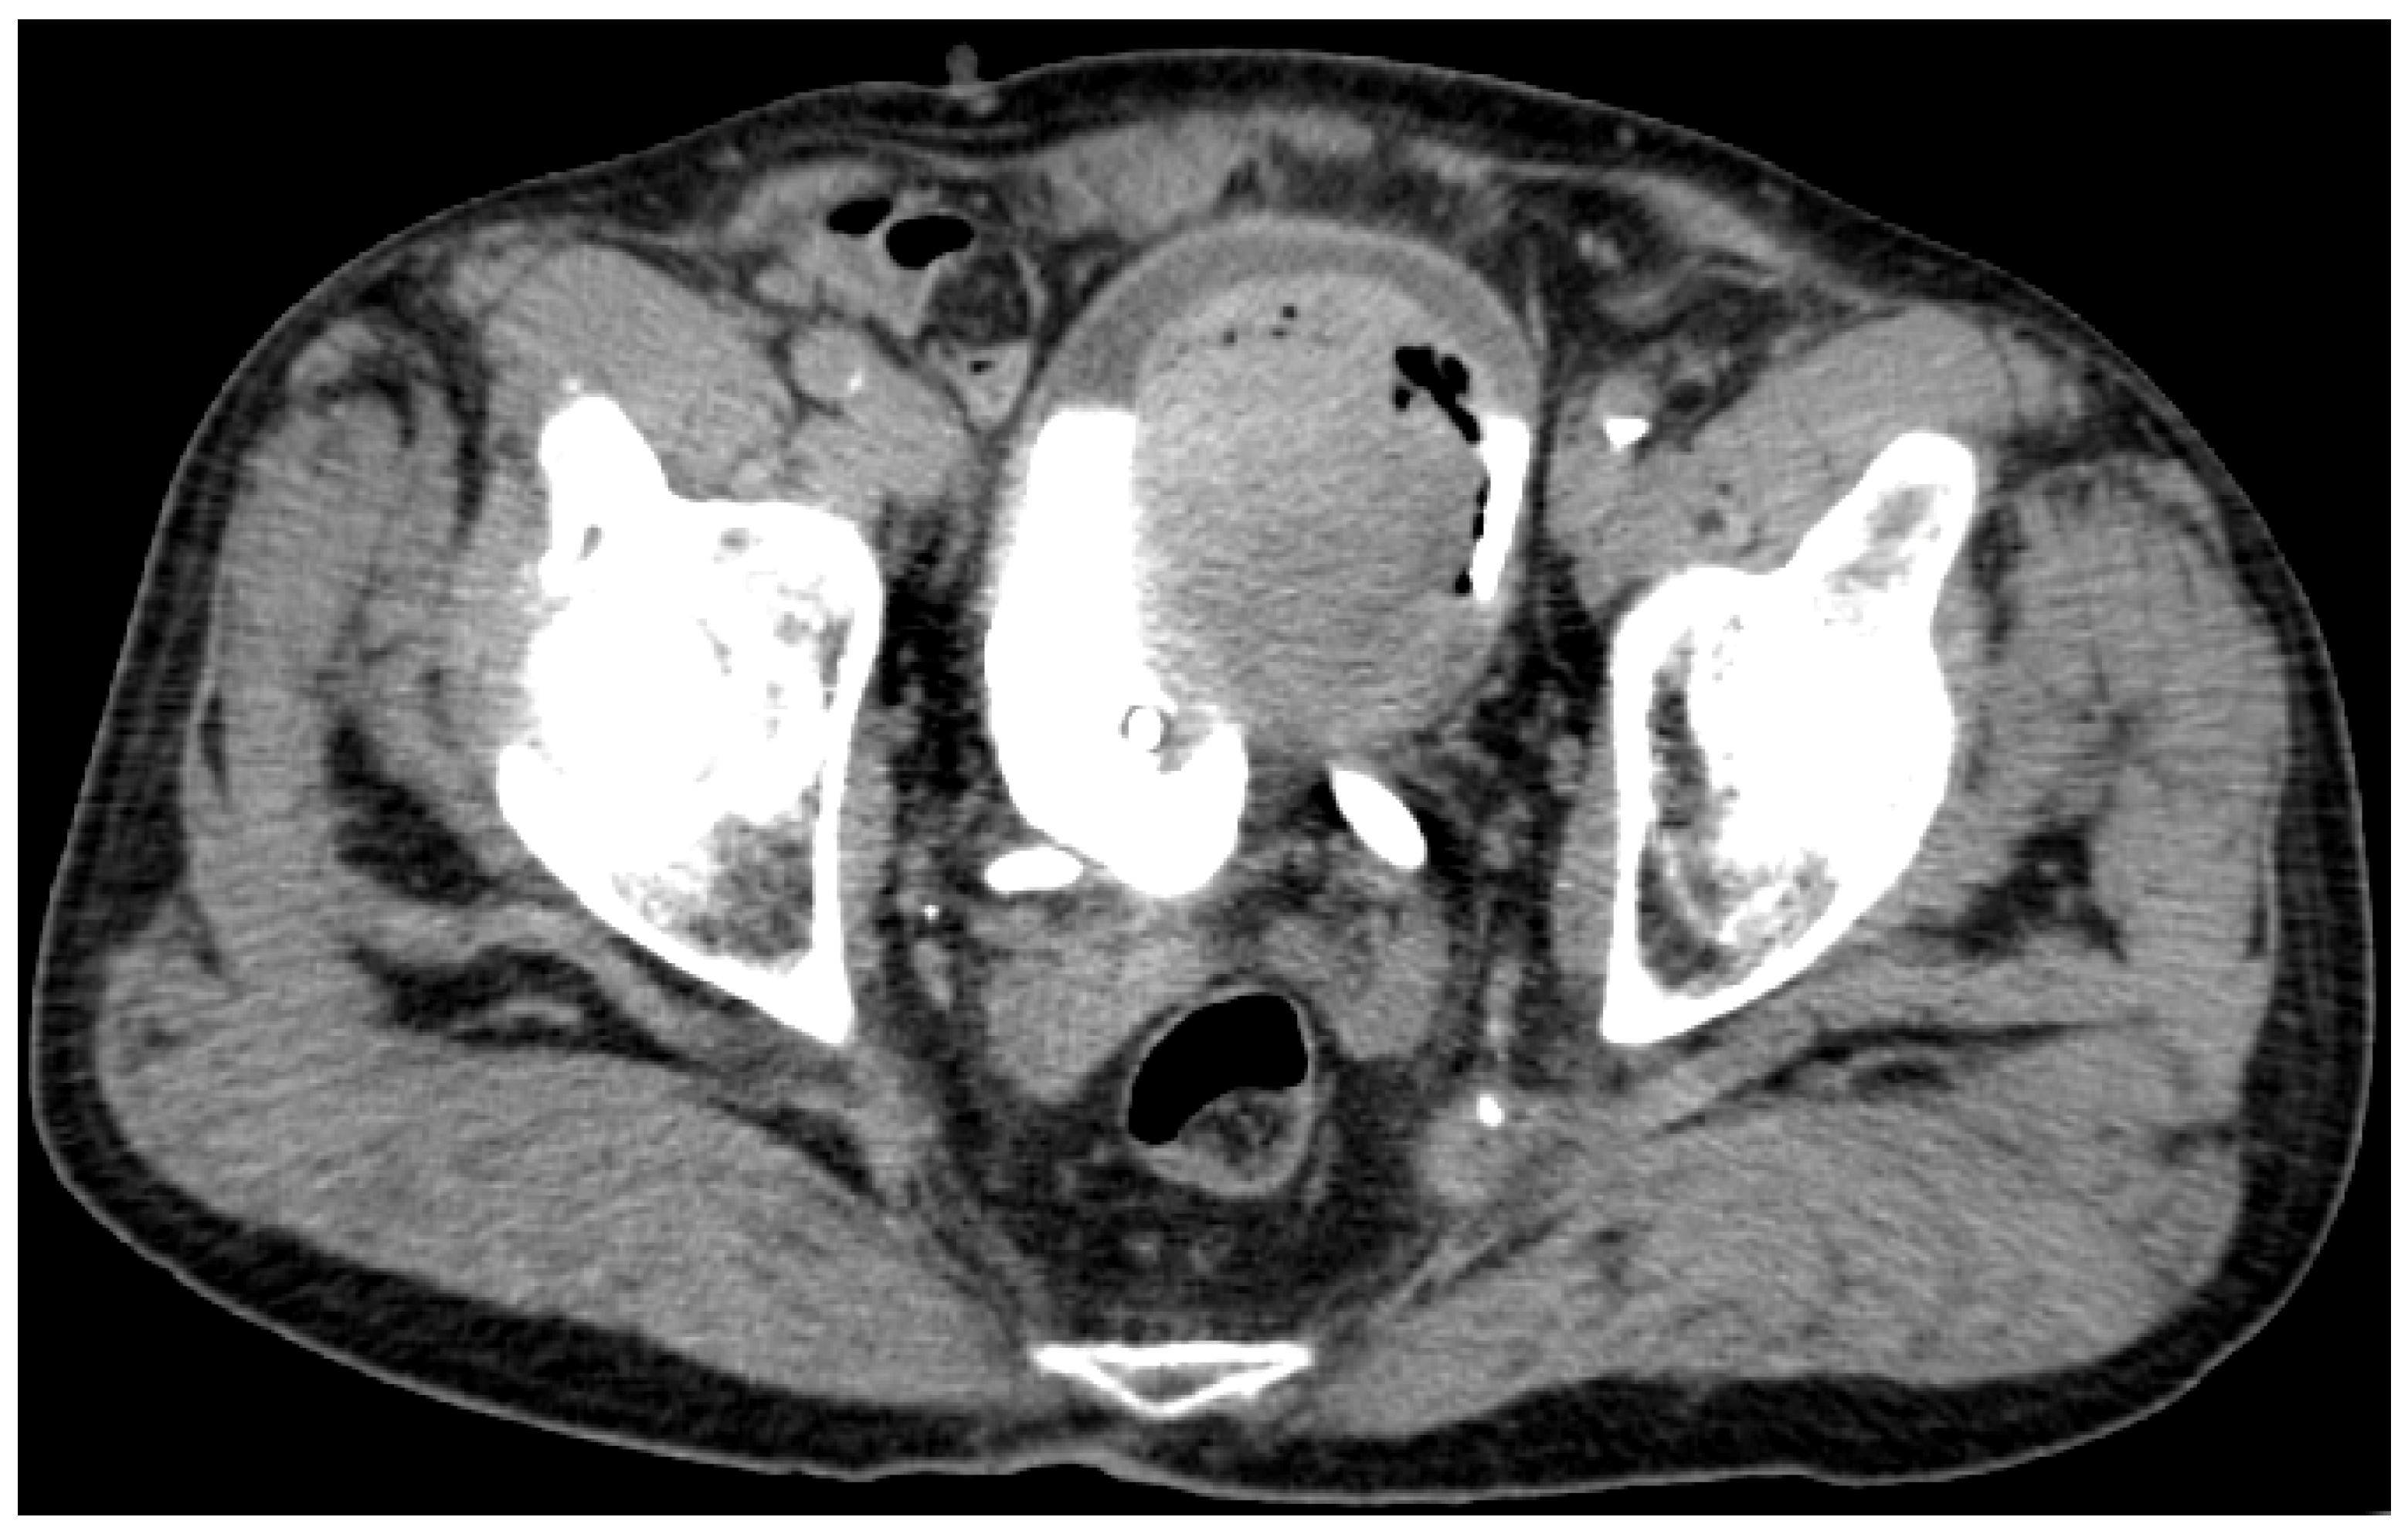

| Date | Procedure | Findings | Concomitant Treatment 1 |

|---|---|---|---|

| 12 July 2019 | TURBT | - pTaG2 high grade; - muscularis propria absent. | Dabrafenib + Trametinib |

| 2 June 2020 | TURBT | - pTaG2 high grade, but with residual tumor; - muscularis propria present. | Nivolumab |

| 9 July 2020 | TURBT | - pT1G2 high grade (biopsy), i.e., large residual tumor. | Nivolumab |

| 30 September 2020 | Cistoscopy | - complete spontaneous tumor necrosis. | Nivolumab |

| 1 February 2021 | TURBT | - pT1G2 high grade, with focal squamous features; - muscularis propria absent. | Nivolumab |

| 23 March 2021 | Radical Cystectomy | - pTaG2 high grade, “early urothelial carcinoma”, R0; - N0 (34 lymph nodes); - incidental prostatic adenocarcinoma, GS 3 + 3 = 6, pT2a | Nivolumab |